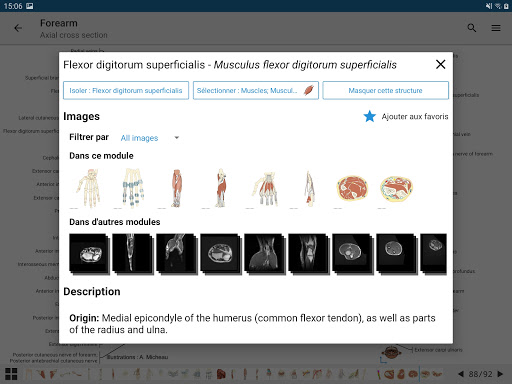

*Improved detail view of anatomical parts for easier identification in images of the current and other modules.

- “Filter by”, in the details view you can now filter the images containing the anatomical structure by modality

- “Filter by”, in the details view you can now filter the images containing the anatomical structure by modality

- You can now hide structures one by one (new button inside the description popup) and display them again in the right menu